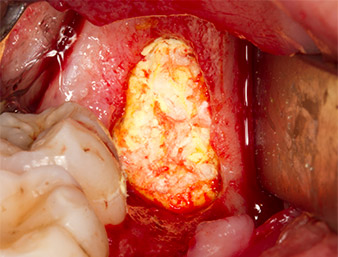

Tras una anestesia local y por conducción, el campo quirúrgico se abrió mediante los tejidos blandos para tener un acceso bucal-retromolar y se dejó expuesto (figura 3).

El tejido situado por encima del resto radicular no se había osificado por completo y constaba en su mayor parte de un tejido granulado con alteraciones inflamatorias (figura 4).